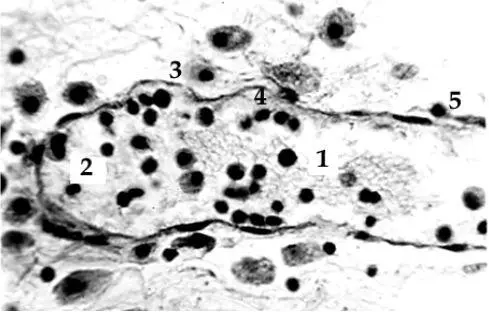

Лимфатический капилляр почки: 1 – полость; 2–5 – клетки на разных этапах миг-рации через эндотелиальную стенку. Желез-ный гематоксилин